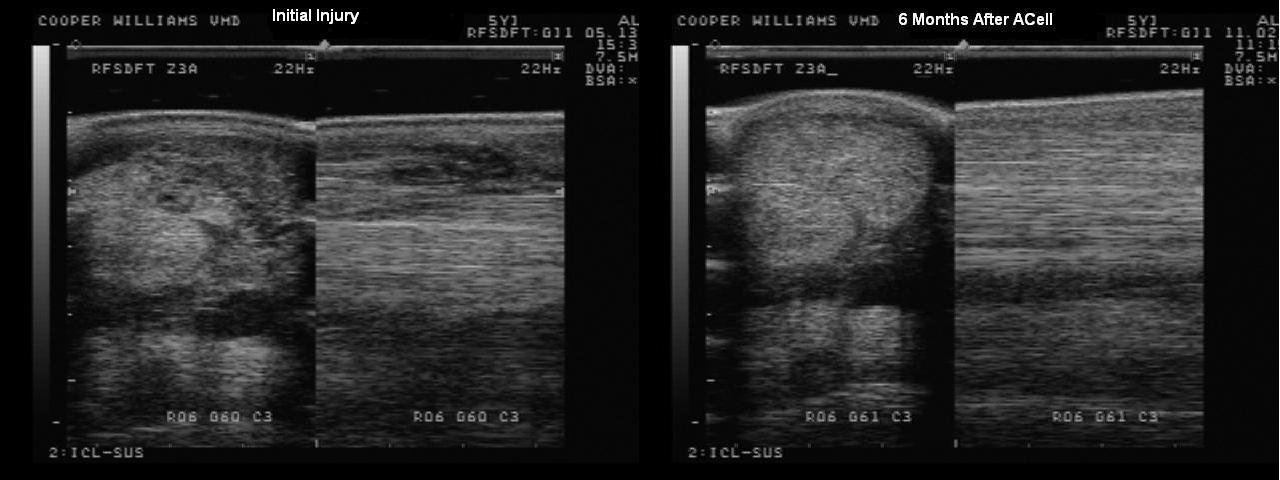

Micro Matrix, formerly ACell Vet, is a tissue reparative product that uses extra-cellular matrices to promote the healing of tendon and ligament injuries without scar tissue. Basically, it triggers a response in the body to fix an injury with the tissue that was intended to be there, instead of the body’s normal injury response of healing through growing scar tissue.

Normally a tendon or ligament injury heals with scar tissue, which has poor fiber alignment similar to cutting parts of a steel cable then trying to fold them back together again. Because of this lack of fiber alignment, the healed injury has lost strength compared to an undamaged fiber alignment. When Micro Matrix is injected into the damaged area it promotes healing without the development of scar tissue. This healing creates a better alignment of fiber that results in a stronger heal similar to that of an undamaged tendon.

Every injury is slightly different, so healing time depends on the specific injury, but the process does seem to accelerate the healing process compared with just time off.